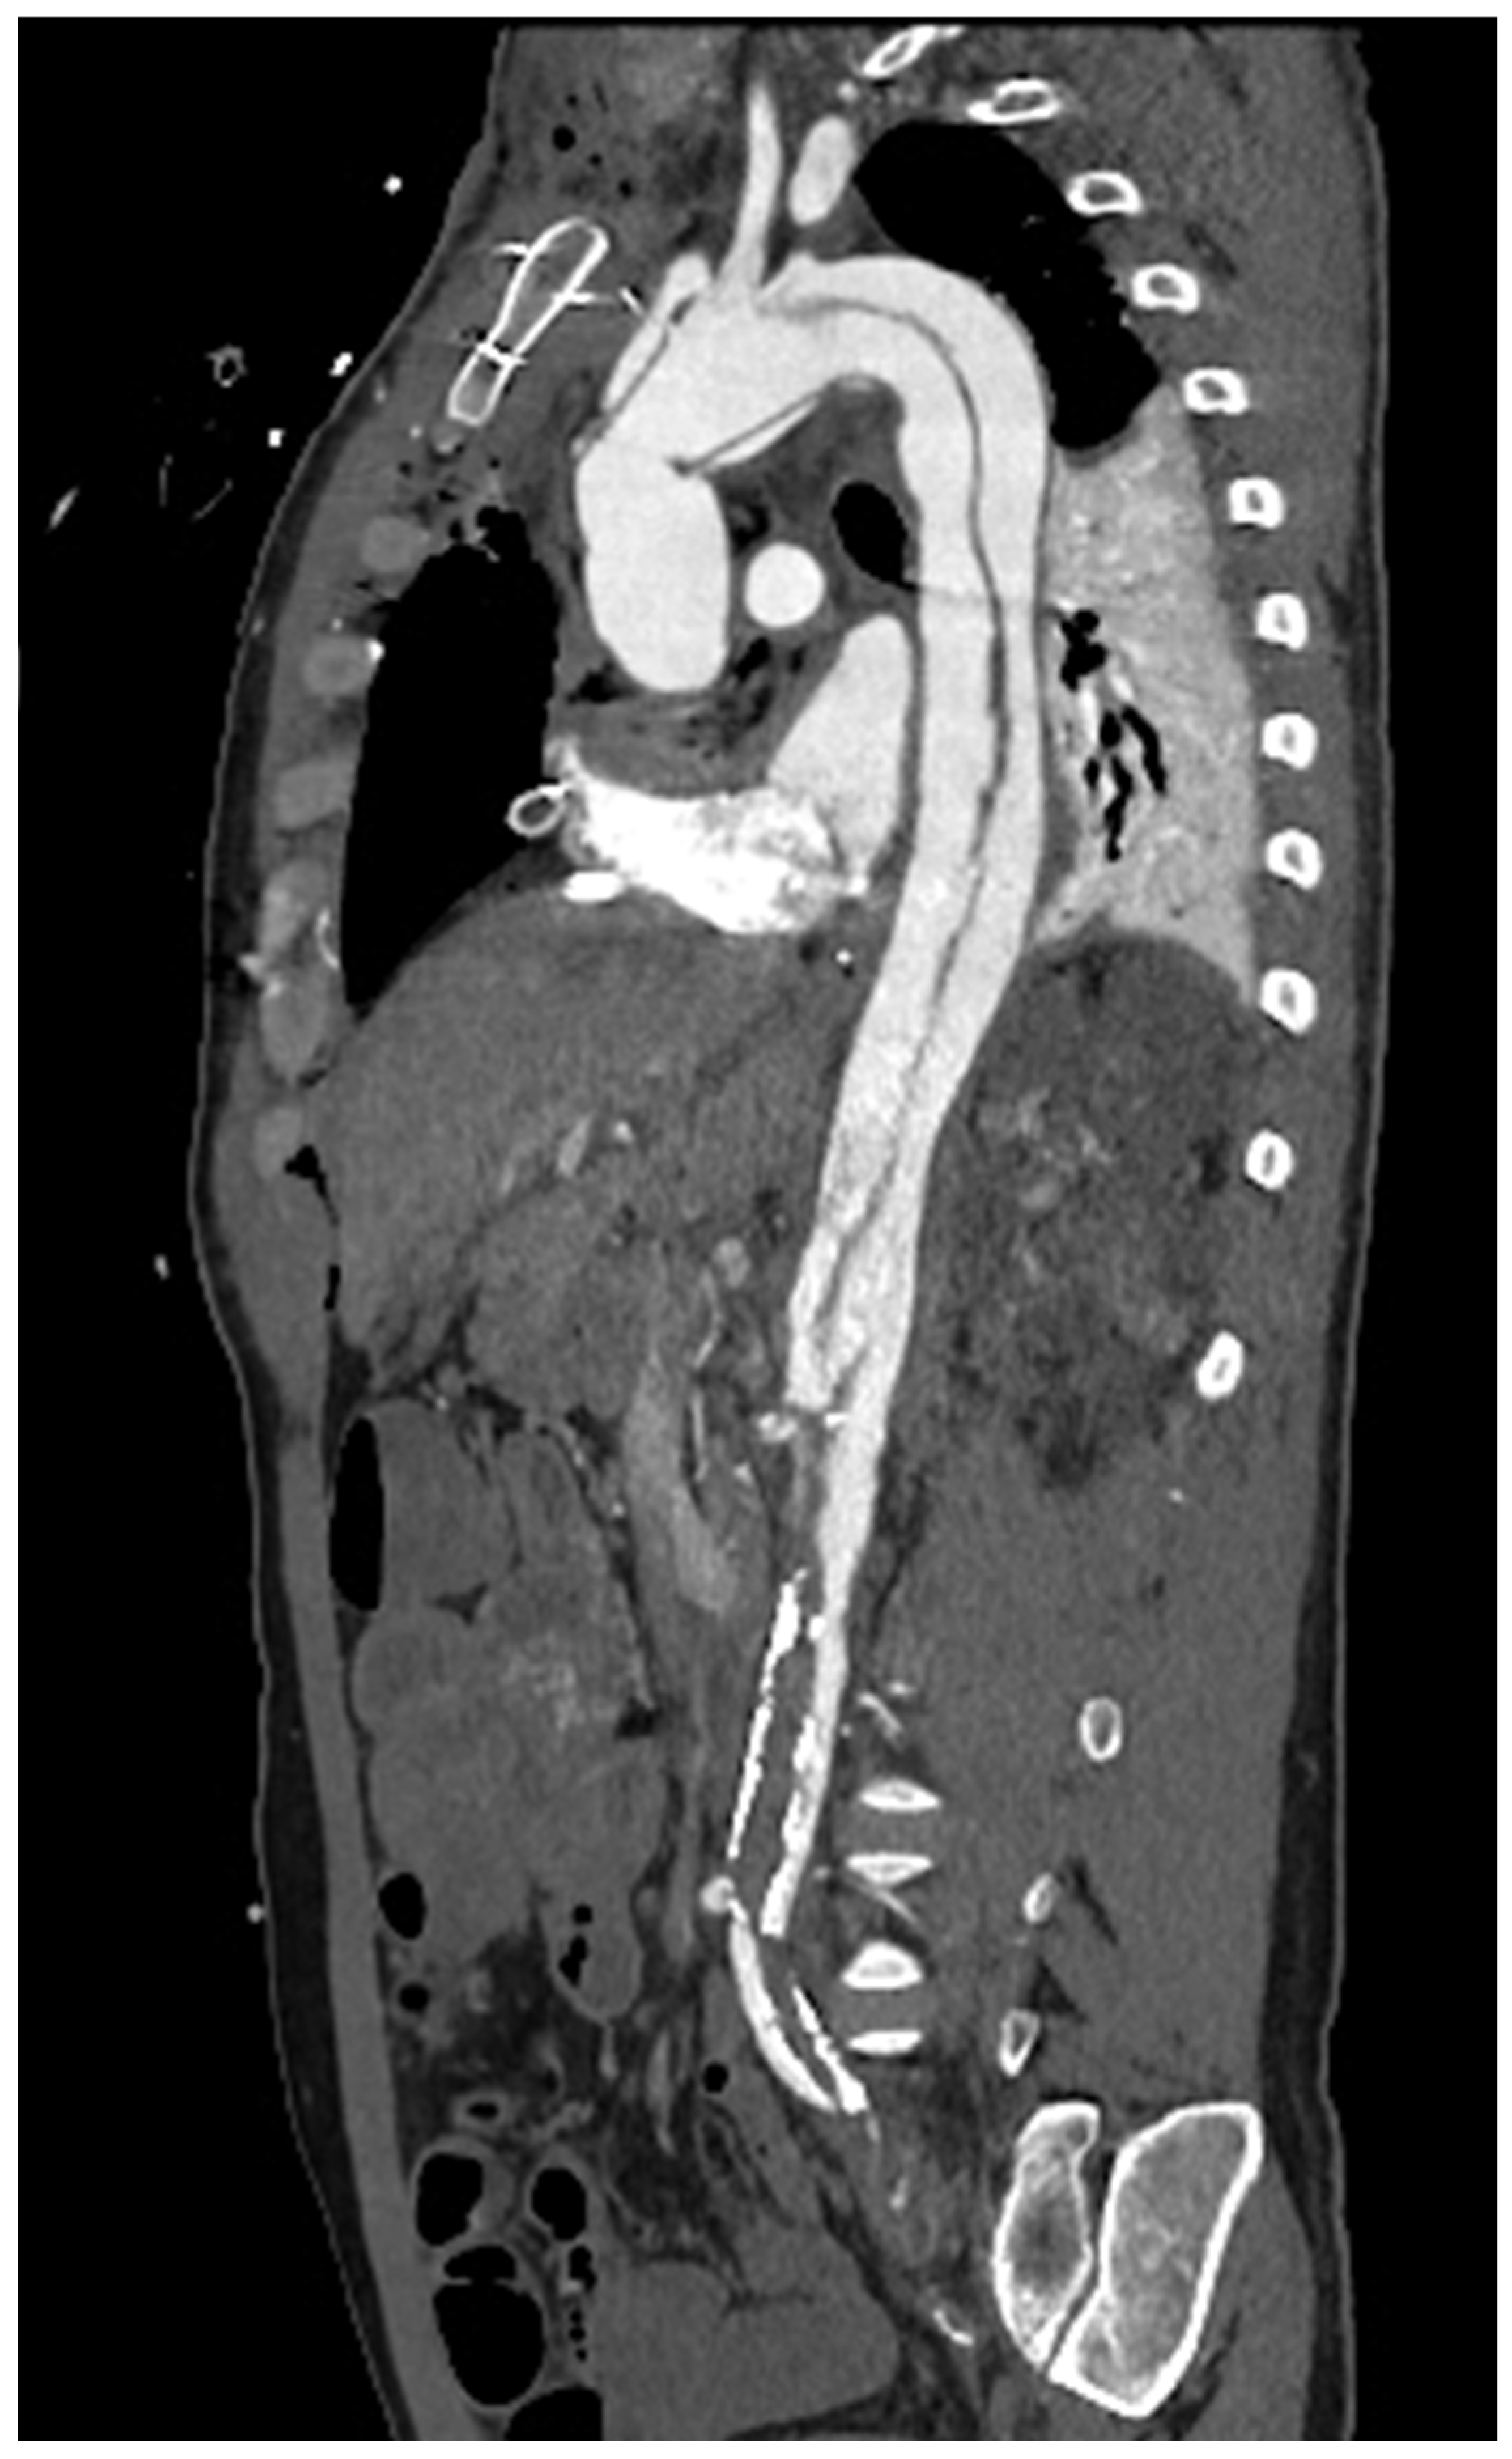

2. Vascular Imaging

- Wielandner, A.; Beitzke, D.; Schernthaner, R.; Wolf, F.; Langenberger, C.; Stadler, A.; Loewe, C. Is ECG triggering for motion artefact reduction in dual-source CT angiography of the ascending aorta still required with high-pitch scanning? The role of ECG-gating in high-pitch dual-source CT of the ascending aorta. Br. J. Radiol. 2016, 89, 20160174. [Google Scholar] [CrossRef]

- Francone, M.; Budde, R.P.J.; Bremerich, J.; Dacher, J.N.; Loewe, C.; Wolf, F.; Natale, L.; Pontone, G.; Redheuil, A.; Vliegenthart, R.; et al. CT and MR imaging prior to transcatheter aortic valve implantation: Standardisation of scanning protocols, measurements and reporting—A consensus document by the European Society of Cardiovascular Radiology (ESCR). Eur. Radiol. 2020, 30, 2627–2650. [Google Scholar] [CrossRef]

- Guo, Y.; Chen, X.; Lin, X.; Chen, L.; Shu, J.; Pang, P.; Cheng, J.; Xu, M.; Sun, Z. Non-contrast CT-based radiomic signature for screening thoracic aortic dissections: A multicenter study. Eur. Radiol. 2021, 31, 7067–7076. [Google Scholar] [CrossRef]

- Wang, Y.; Xiong, F.; Leach, J.; Kao, E.; Tian, B.; Zhu, C.; Zhang, Y.; Hope, M.; Saloner, D.; Mitsouras, D. Contrast-enhanced CT radiomics improves the prediction of abdominal aortic aneurysm progression. Eur. Radiol. 2023, 33, 3444–3454. [Google Scholar] [CrossRef] [PubMed]